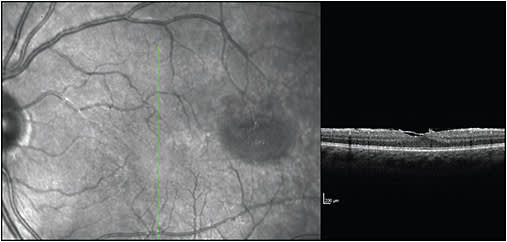

Other complications include glaucoma, posterior synechiae, cataract, epiretinal membrane, vitreous hemorrhage, retinal periphlebitis, retinal neovascularization, macular edema, subretinal fluid, and traction retinal detachment. Glaucoma and cataract, of course, may also be secondary to corticosteroid therapy in the treatment of uveitis. Figures 1-5 show examples of some of these sequelae of MS-associated uveitis. While macular edema in MS is usually secondary to uveitis, or occasionally to the use of fingolimod,33,34 Gelfand35 found that 15 of 318 (4.7%) patients with MS had microcystic retinal edema with no other risk factors, such as uveitis or retinal vascular occlusion. In addition, patients with macular edema had worse vision, worse disability scores, and higher MS severity scores than patients without macular edema. The edema was more common in patients with prior episodes of optic neuritis.